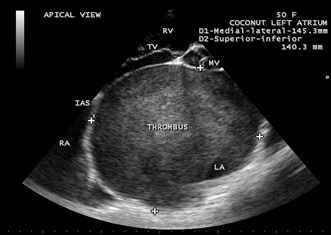

Case 5. Giant left atrium with dense SEC (spontaneous echo contrast) visible as massive thrombus occupying the entire giant left atrium and resembling as “coconut atrium” as shown in Figures 21 to 25 and movie in Figure 26

in rheumatic mitral stenosis in a 50- year old female. Patient was advised lifelong penicillin prophylaxis, Redo MVR (mitral valve replacement) and removal of thrombus with inverted T-shaped biatrial incision (endoatriectomy- transeptal superior approach)

Figure 24. Tilted apical view showing the giant thrombosed left atrium in a 50-year-old female resembling as a “coconut” as in Figure 25

Figure 25. showing the “coconut”.

Massive calcification of left atrium, predominantly affects the woman (74%) and it tooks an average duration of 19.7 years (17-20 years) to become manifest in rheumatic mitral stenosis and resembled a coconut shell [72]. The term ‘coconut atrium’ is misnomer to describe this condition and a complete opacification of giant left atrium with dense SEC seen as thrombus as shown in Figure 24, resembling a ‘coconut’ as in Figure 25 and this condition is better termed as ‘coconut atrium’ appropriately.